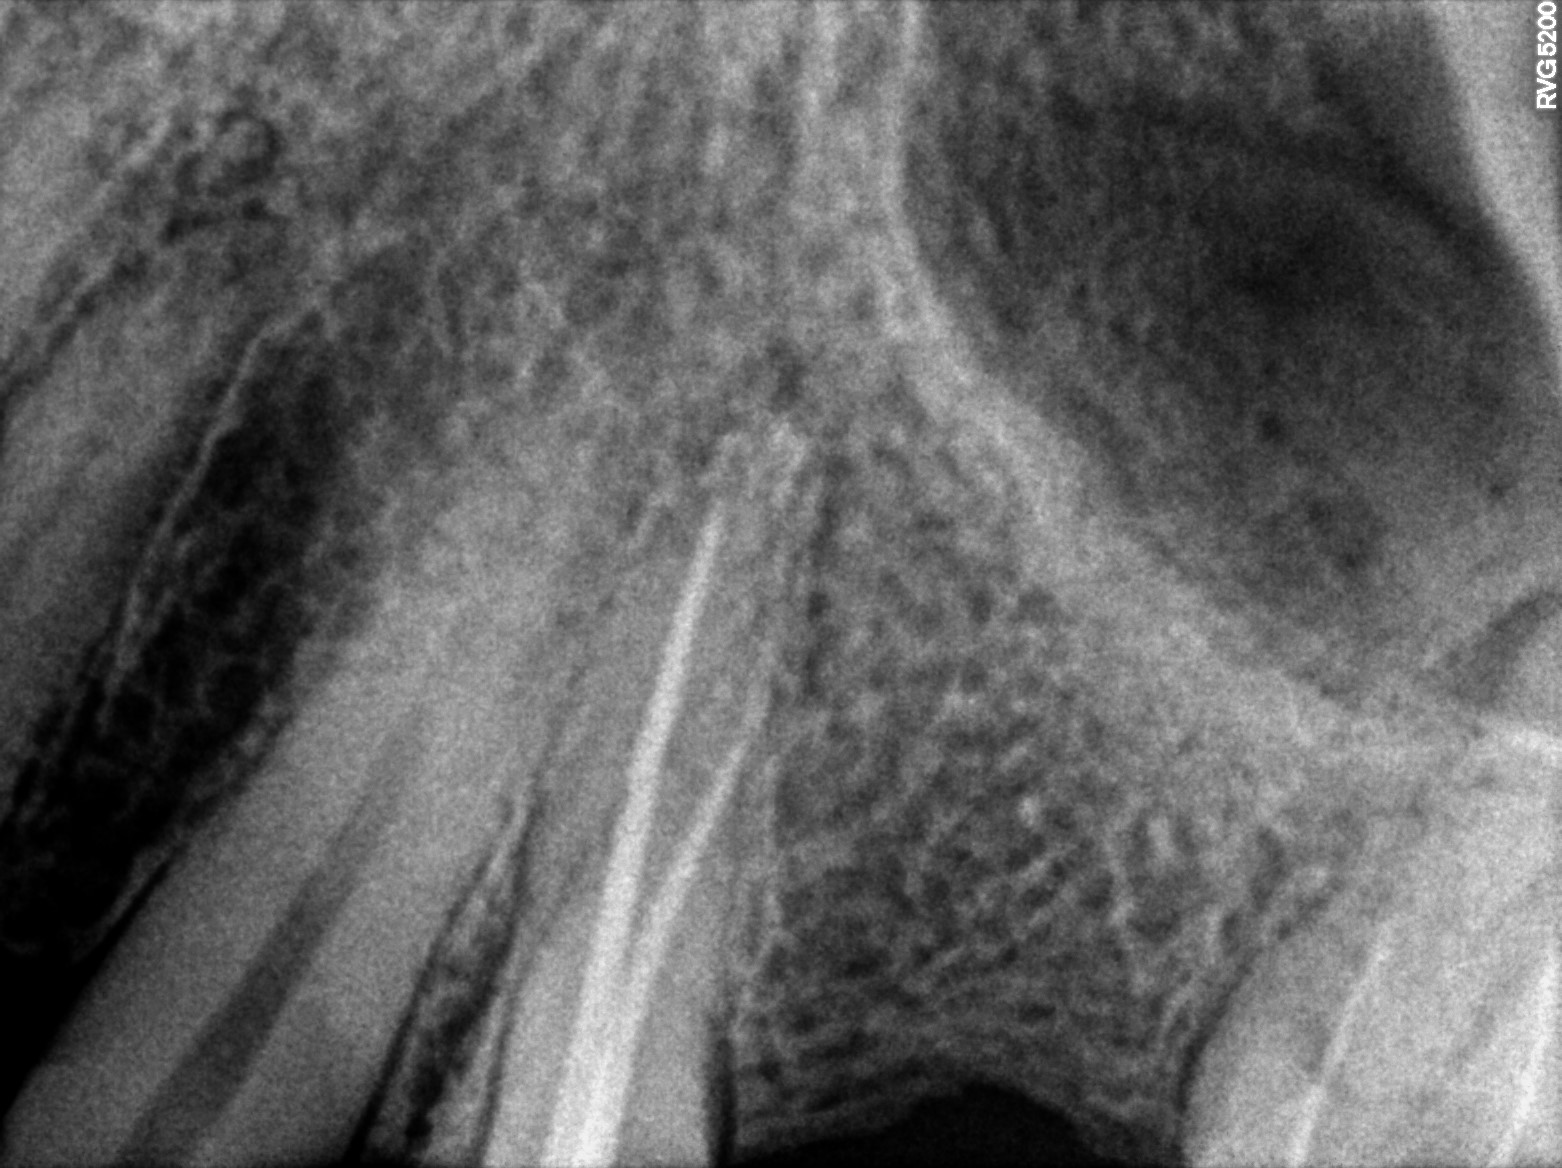

Dental Radiographs FHIR: DocumentReference · LOINC 24641-7

2 (1).jpg

24641-7